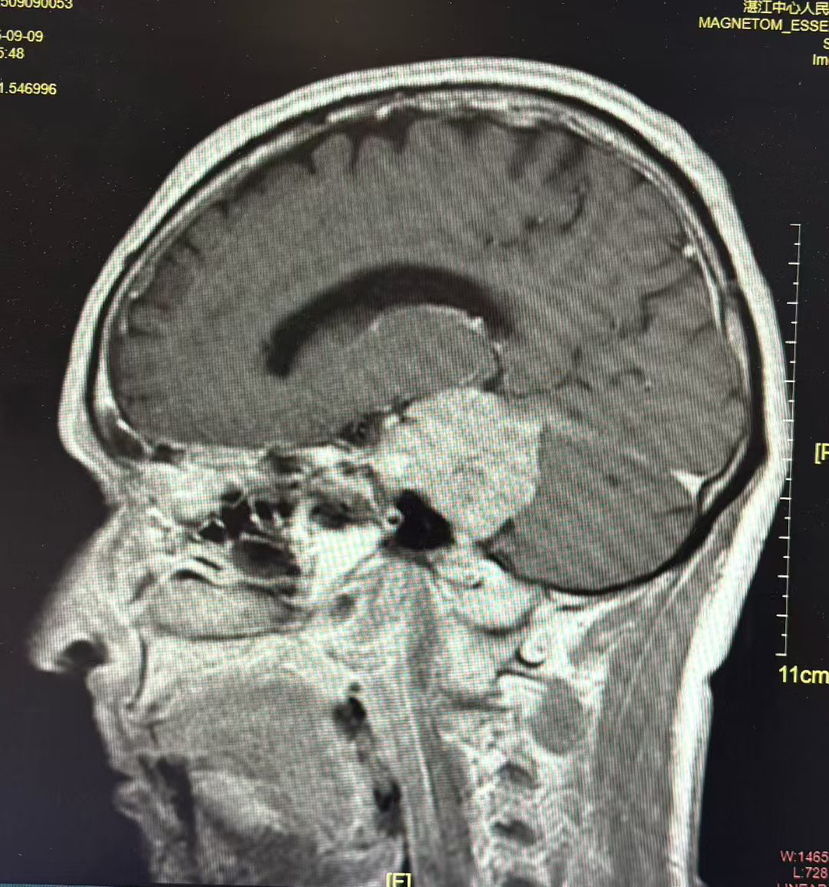

术前MRI